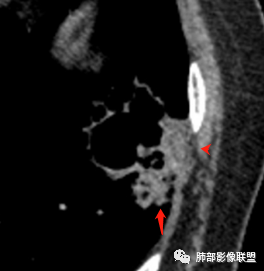

病灶分两部分

周围大片GGO

中央囊实性病变

南边:

病史没提咳血,周围出血灶似乎不太好说

部分边界偏清

囊腔有张力,外形有分叶,壁厚薄不均,有间隔,有强化

哪些病变可能?

1、癌

2、炎性:曲霉菌?

3、良性:囊腺瘤样畸形合并感染

1、左肺下叶外基底段不规则囊腔样病灶,囊腔内有条形影及血管穿行。

2、囊壁薄厚不均匀,稍显僵硬,有壁结节(对应边缘分叶等)、结节强化明显。

以上两条几乎将肺囊肿彻底排除在外,且高度怀疑新生物!

3、灶周环以大范围磨玻璃影,非常均匀,没有重力分布趋势,分叶状,边界隐约可变。

4、冠状位部分层面可见支气管在囊腔边缘截断。